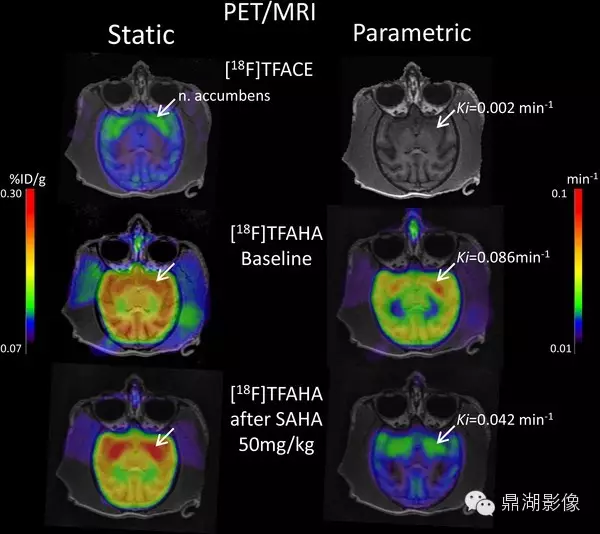

这是一个例对灵长类动物的分子影像学研究

4.Scientific Session 13: Central Nervous System

September 9, 2011:PET/CT/MRI with [18F]TFAHA using an optimized pharmacokinetic model for quantification of HDAC class II expression-activity in the brain in non-human primates